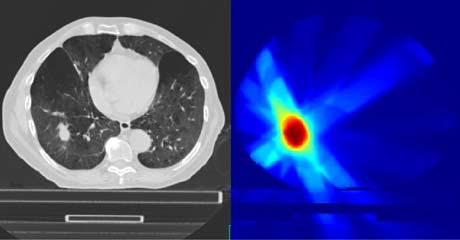

El cálculo de la dosis en los tratamientos de radioterapia externa es un desafío por la alta conformación de los haces de radiación en la tecnología actual (IMRT y VMAT). Estas técnicas adaptan los haces a la forma del tumor, de manera que la dosis recibida por los tejidos sanos es pequeña, pero el coste asociado es que cualquier error de posicionamiento o el movimiento del propio tumor (por ejemplo, por respiración) puede afectar a la dosis depositada.

Esta línea tiene por objeto  utilizar herramientas de adquisicón de imagen (Cone Beam CT) y de procesado de imagen médica (registro deformable) para determinar la dosis real recibida por un paciente en cada sesión de tratamiento y así poder adaptar las sesiones restantes para alcanzar la dosis prescrita.

La dosis recibida por el tejido sano es de especial importancia cuando los pacientes son pediátricos o cuando se van acumulando tratamientos radioterápicos. Para este tipo de tratamientos está especialmente indicada la radioterapia con protones, disponible en la sede de Madrid de la Clínica Universidad de Navarra. En esta línea buscamos resolver los problemas asociados al Pencil-Beam Scanning y el movimiento interno del tumor.

En esta línea buscamos optimizar el procedimiento y la dosis en el caso de tumores pulmonares y oculares empleando desarrollos propios tanto de equipamiento como de herramientas computacionales